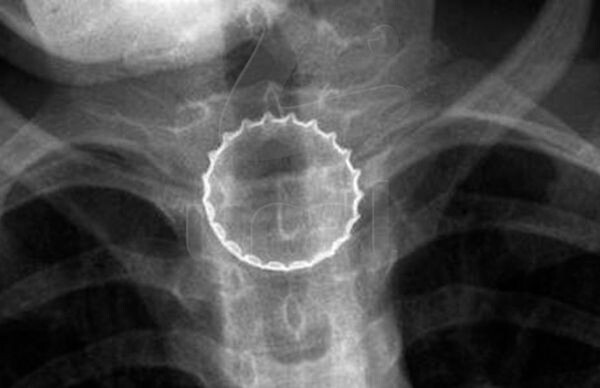

Подросток из Челябинска проглотил металлическую крышку от бутылки

Подросток из Челябинска проглотил металлическую крышку от бутылки. 16-летний школьник поймал железяку губами, та попала в горло и застряла в пищеводе. Потребовалась срочная операция — был риск, что острые края порежут внутренние органы. Хирурги справились, сейчас парень уже дома — со вкусняшками на время придётся расстаться.